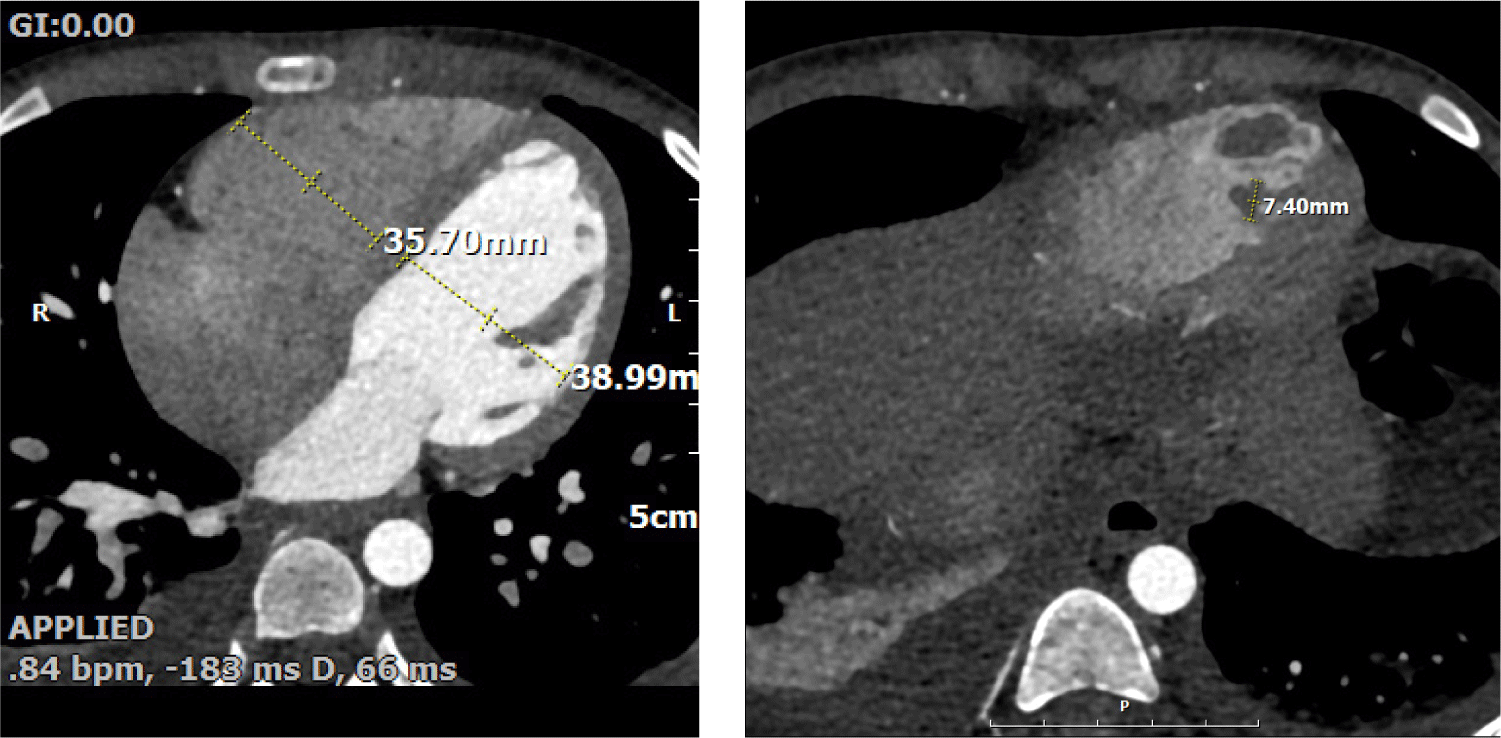

Echocardiography revealed impaired LV systolic function (LVEF 43%, global longitudinal strain −12.5%) and RV dysfunction (TAPSE 10 mm, tricuspid annular S′ 9 cm/s, RVFAC 20%). The inferior vena cava was mildly dilated (17 mm) with poor inspiratory collapse, also indicating deteriorated RV function. A large oval mass (1.5 × 0.7 cm) was visualized at the RV apex (Fig. 2). The mass was suspected to represent either vegetation or thrombus, and cardiac computed tomography (CT) findings favored thrombus over vegetation (Fig. 3). It was hypothesized that a small vegetation may have developed secondary to infection, while reduced RV systolic function caused turbulent flow; together with the prothrombotic tendency associated with SARS-CoV-2 infection, these factors likely accelerated the formation of a larger thrombus.

Fig. 2. Echocardiographic findings of Case 2. Echocardiography revealed two distinct oval-shaped masses measuring approximately 1.5 cm and 0.7 cm located at the right ventricular (RV) apex. (A) Zoom in image for the mass at RV apex, (B) Four chamber view demonstrated the echogenic ovale shaped mass at RV apex.

Fig. 3. Cardiac CT of Case 2. Cardiac CT showed two low-density lesions (1.5 cm and 0.7 cm) within the RV apex, which were more suggestive of thrombus rather than vegetation. CT: computed tomography; RV: right ventricular.